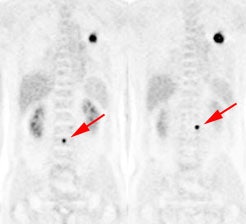

|

Change in stage: The patient below was felt to have Stage IIIB disease based upon the chest CT findings. FDG PET imaging confirmed ipsi- and contralateral mediastinal adenopathy, but also reveal a left scapular metastasis (seen retrospectively on the CT scan [white arrow]). A left iliac metastasis was also identified (black arrow right PET image). This resulted in a change in patient stage as the patient was now has Stage IV disease. |